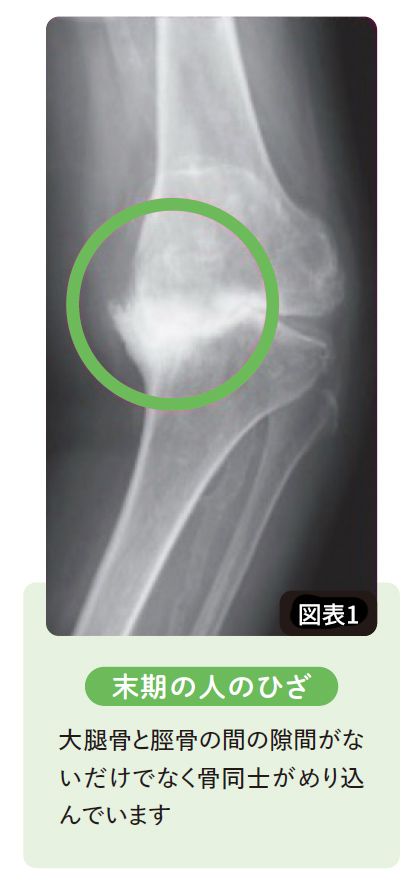

「ひざの軟骨は再生しない」は間違い…日本ではなぜかスタンダードになっている”ひざ痛治療の落とし穴”

出典=巽一郎『

足腰復活100年体操

』より

巽一郎『足腰復活100年体操』(サンマーク出版)